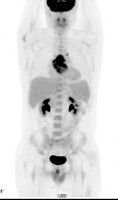

| Инфекционный эндокардит | Инфицированная парапротезная гематома у пациента после протезирования восходящего отдела аорты |